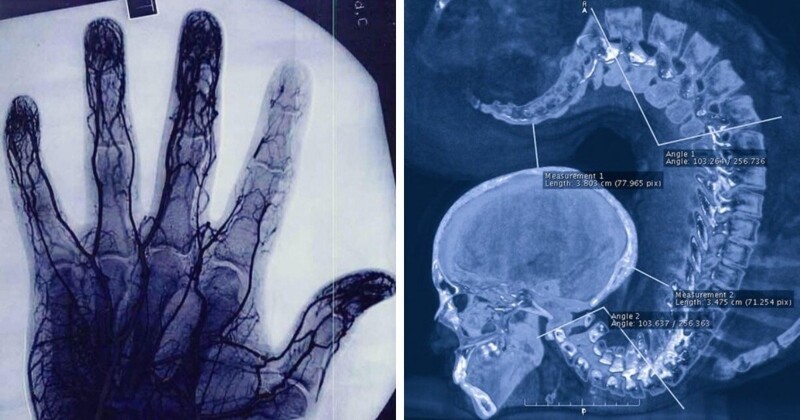

Необычные рентгеновские снимки: то, что скрыто внутри

Раздел: Визуальный дайджест